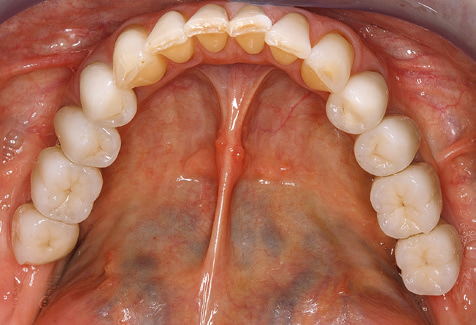

Eine 52-jährige Patientin stellte sich nach Zahnverlust im 3. Quadranten erstmals 2004 vor. Sie hatte den Wunsch nach einer prothetischen Neuversorgung. Im Rahmen der parodontologischen und radiologischen Diagnostik zeigte sich ein ausgeprägter parodontologischer Behandlungsbedarf. Die Zähne 48, 28, 27 zeigten zudem eine infauste Prognose und wurden entfernt (Abb. 1). Nach der erfolgreich abgeschlossenen systematischen PARTherapie wurde eine festsitzende implantatprothetische Versorgung mit Insertion von fünf Implantaten in Regio 35, 36, 37 und 46, 47 durchgeführt. Die prothetische Versorgung der natürlichen Zähne erfolgte mit verblendeten Zirkonoxidkeramikkronen, die Implantate wurden mit zweiteiligen individuellen Zirkonoxidabutments und ebenfalls verblendeten Kronen aus einer Zirkonoxidkeramik versorgt (Cercon base colored, Dentsply Sirona Lab). Die definitive Insertion der prothetischen Versorgung erfolgte im Jahr 2005.

Aufgrund der bestehenden parodontalen Vorerkrankung erfolgte die unterstützende Parodontaltherapie (UPT) in den ersten Jahren in einem DreiMonatsIntervall. Dabei zeigte die Patientin eine hohe Motivation und gute Compliance. Bei den jährlich erhobenen Sondierungsbefunden zeigten sich stabile parodontale Verhältnisse mit einem BOPIndex unter fünf Prozent. Aufgrund der stabilen parodontalen Situation und der guten Mitarbeit der Patientin wurde ab dem sechsten Jahr der prothetischen Funktionsphase das Recallintervall auf halbjährlich umgestellt. Auch mit diesem veränderten Recallintervall zeigten sich bei der jeweils jährlichen Aufnahme des Parodontalstatus stabile parodontale Verhältnisse, ohne Zunahme der Sondierungstiefen und einem BOPIndex unter fünf Prozent (Abb. 2a und b).

Im Rahmen der ZehnJahresKontrolle zeigten sich keine Hinweise auf einen fortschreitenden parodontalen Attachmentverlust oder einen periimplantären Knochenverlust (Abb. 3).

Für den klinischen Langzeiterfolg des parodontal kompromittierten Patienten ist die standardisierte und regelmäßige risikoadaptierte Betreuung im Rahmen der UPT der zentrale Baustein des Behandlungserfolgs. Dies gilt in besonderer Weise für Patienten, die nach erfolgreich abgeschlossener parodontaler Sanierung mit Implantaten versorgt wurden (Abb. 11a und b).